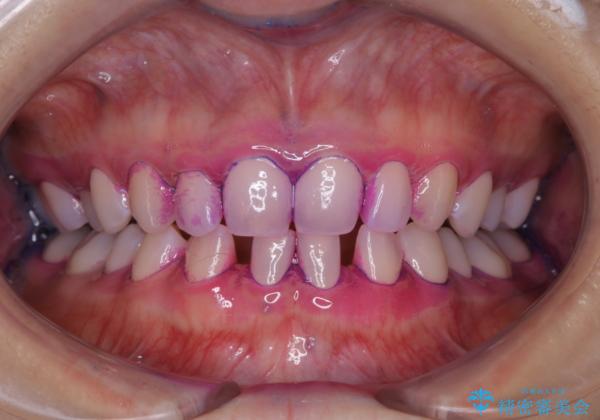

- すき間の部分の歯磨きがしずらく、クリーニング希望で来院されました。今後はセラミックによる治療を考えてとの事でした。PMTC(保険外治療)30分コースを行いました。

PMTC(保険外治療)とは、歯垢・歯石・着色などを除去することです。磨きのこしなどにより歯垢が付着し続けると、歯石に変化していきます。歯石になってしまったら、歯ブラシだけで落とすことができなくなります。そのため歯科医院での専門的な機械・材料を使用してのクリーニングが必要です。